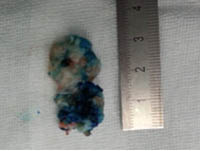

术中所取出的髓核组织 术中所看到的神经根